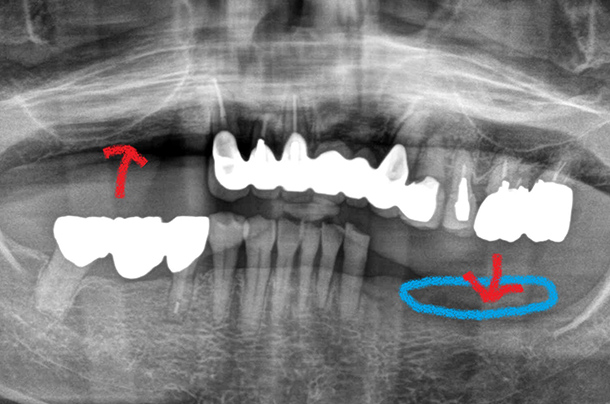

すれ違い咬合に近い噛み合わせの義歯治療

左右の奥歯が互い違いで残っている患者様です。このようなお口では義歯にシーソーのような強い力がかかります(赤矢印)。強い力のかかる顎の骨は痩せていきます(水色の箇所)。保険の義歯では、義歯がたわんでしまうため、義歯の動きをコントロールできません。そのため上下に金属床義歯を作製することで、義歯の大きさを出来るだけ薄く、小さくし、しっかり噛めるように回復しました。